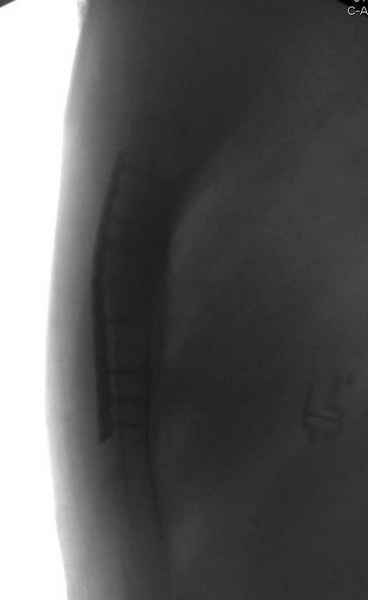

После торакальной операции, по-видимому, сильно натянули проволоку, и в результате получился захлест отломков в друг друга.

Оперировавший хирург предлагает подождать, а родителей беспокоит проблема прогрессирующей ассиметрии лица, как при кривошее.

С такими продольными несращениями мне не приходилось иметь дело, поэтому направил в один из центральных институтов детской ортопедии России.